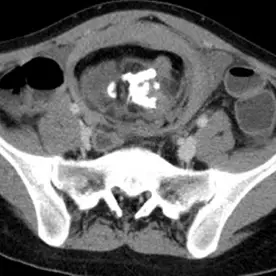

Die kontrastmittelverstärkte CT des Beckens zeigt eine 10 x 10 x 13cm große Raumforderung mit dicker Wand mit teils lipomatösen, teils nicht lipomatösem weichteiläquivalentem Inhalt, im Zentrum der Raumforderung besteht zudem eine Ossifikation (Pfeile), die den Aspekt einer Kieferanlage mit reifen Zähnen besitzt. Der CT-morphologische Verdacht eines reifen Teratoms. Bild einer Stieldrehung mit venöser Kongestion und Nekrose des betroffenen Adnexes.

CT-morphologischer Verdacht eines reifen Teratoms . Die klinische Symptomatik ist durch eine Stieldrehung mit venöser Kongestion und Nekrose des betroffenen Adnexes erklärbar.